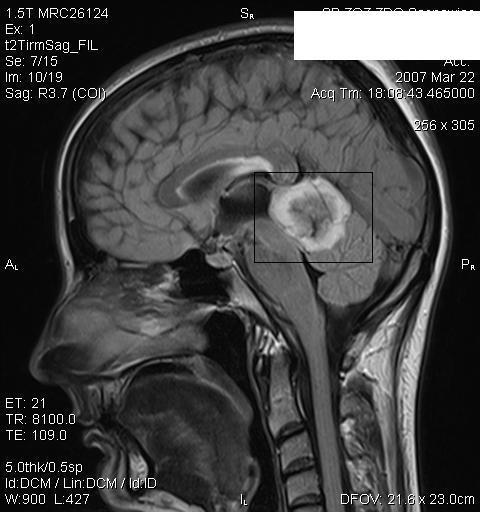

We present two cases of a disease: a case of a 49-year-old woman with a typical image of hemifacial atrophy, without any changes of the nervous system and a case of a 33-year-old patient with an "en coup de sabre" scleroderma and with CNS tumor.

We described typical cases of a rare diseases, hemifacial atrophy and "en coup de sabre" scleroderma. In the patient diagnosed with Parry-Romberg syndrome, with Borrelia burgdoferi infection and with minor neurological symptoms, despite a four-year case history, there was a lack of proper diagnosis and treatment.In the second patient only skin changes without any neurological symptoms could be observed and only a precise neurological diagnosis revealed the presence of CNS tumor.

我们展示了该疾病的两个病例:一例是一名49岁女性,具有典型的半侧面部萎缩影像,神经系统无任何变化;另一例是一名33岁患者,患有“剑伤样”硬皮病且伴有中枢神经系统肿瘤。

我们描述了罕见疾病半侧面部萎缩和“剑伤样”硬皮病的典型病例。在被诊断为帕里-罗姆伯格综合征、感染伯氏疏螺旋体且有轻微神经症状的患者中,尽管有四年病史,但仍缺乏正确的诊断和治疗。在第二名患者中,仅观察到皮肤变化而无任何神经症状,只有精确的神经诊断才发现存在中枢神经系统肿瘤。